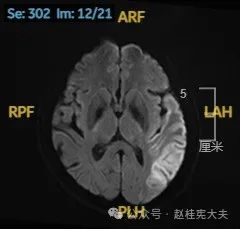

入院后给予精氨酸,左卡尼丁,辅酶Q10,维生素E等治疗。患者病情稳定好转中,2天后意识清楚,语言表达仍欠佳。当天复查颅脑磁共振如下:

以上为患者发病后3次的颅脑磁共振片子,临床诊断基本上可以确认了,希望患者逐渐恢复!